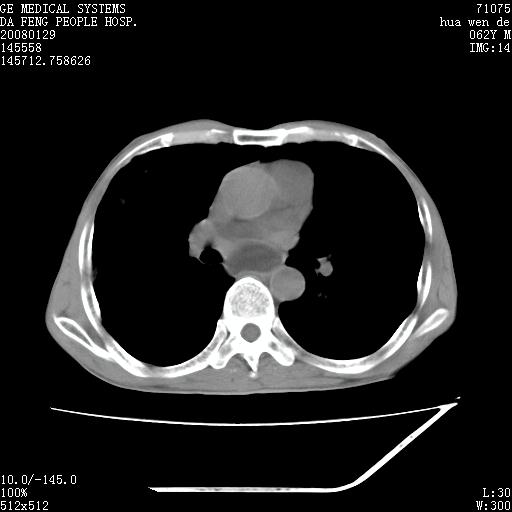

男性,67岁。作肺部检查时发现

理由:1、右上肺内病灶,空洞形成,有液平。

2、肺内多处炎症。

1.整个食管扩张,未见明显占位性病变,贲门区亦未见明显占位病变,考虑:贲门失驰缓症;

2.右上肺病变边缘可见毛刺,囊壁厚度不均匀,周围境界较清楚,未见炎性渗出性影,右上肺外带可见片状影,边缘不清,考虑:肺癌伴空洞形成、右上肺炎。

食管全程扩张,壁均匀不厚,喷门失弛缓症

右上肺空洞可见液平,临近肺野磨玻璃密度,考虑1.结核2.脓肿

贲门失驰缓症.肺部感染伴脓肿形成。支持!是否吸入性要结合临床诊断,我们影像是看不出来的。但胸腔胃能排除(1.没有手术史支持,2.双侧胸廓对称,胸壁、肋骨及胸膜规整,3,食管壁明显扩张内壁光滑,胸腔胃黏膜皱襞多较厚)。